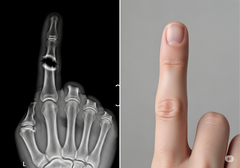

Podejście Bone Biologics koncentruje się na białku NELL-1, czynniku wzrostu, który jest naturalnie zaangażowany w rozwój kości. Badania przedkliniczne wykazały, że NELL-1 jest wyjątkowo zdolny do stymulowania silnego wzrostu kości dokładnie tam, gdzie jest to potrzebne, jednocześnie hamując tworzenie się komórek tłuszczowych, co jest częstym problemem w przypadku innych leków biologicznych. To ukierunkowane działanie może prowadzić do bardziej niezawodnych fuzji i mniejszej liczby powikłań.